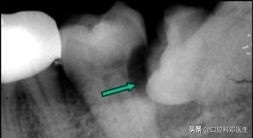

在远古时代,由于贫穷,伙食差,人类都不给他作案的机会,有足够的位置让他长出来,到了现代,随着伙食的精细,智齿常常发育不良,不是东倒就是西歪,为了报复主人,时不时发炎疼痛,让主人记住我,或者挖洞,把兄弟给祸害!

智齿行凶过程图